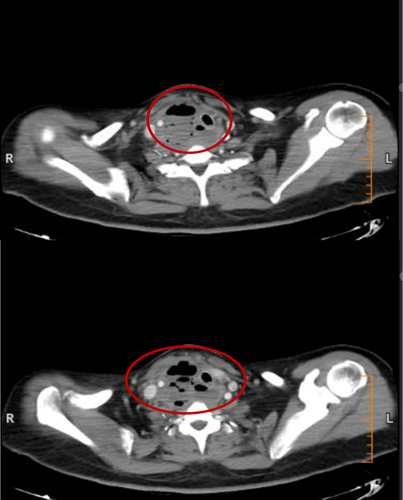

2月15日与20日,当整座城市沉浸在辞旧迎新的欢声笑语中,两位病情凶险的颈部深部脓肿患者先后被推入耳鼻咽喉头颈外科。他们都有多年糖尿病病史,春节期间饮食不规律、作息紊乱、血糖波动大,让原本隐匿的感染如野火般迅速蔓延。其中一位患者的感染已突破颈部间隙,如藤蔓般向下侵入纵隔区域——那里是心脏、大血管、气管的“交通枢纽”,是人体最脆弱的生命禁区之一。CT影像上,脓肿中密布的气腔像一个个危险的信号,气管被严重受压,每一次呼吸都变得艰难。文献数据冰冷而沉重:颈深部脓肿并发下行性纵隔炎,病死率高达40%~70%。时间,从未如此紧迫。

患者甲CT示:颈部及纵隔脓肿,脓肿中含有多个气腔